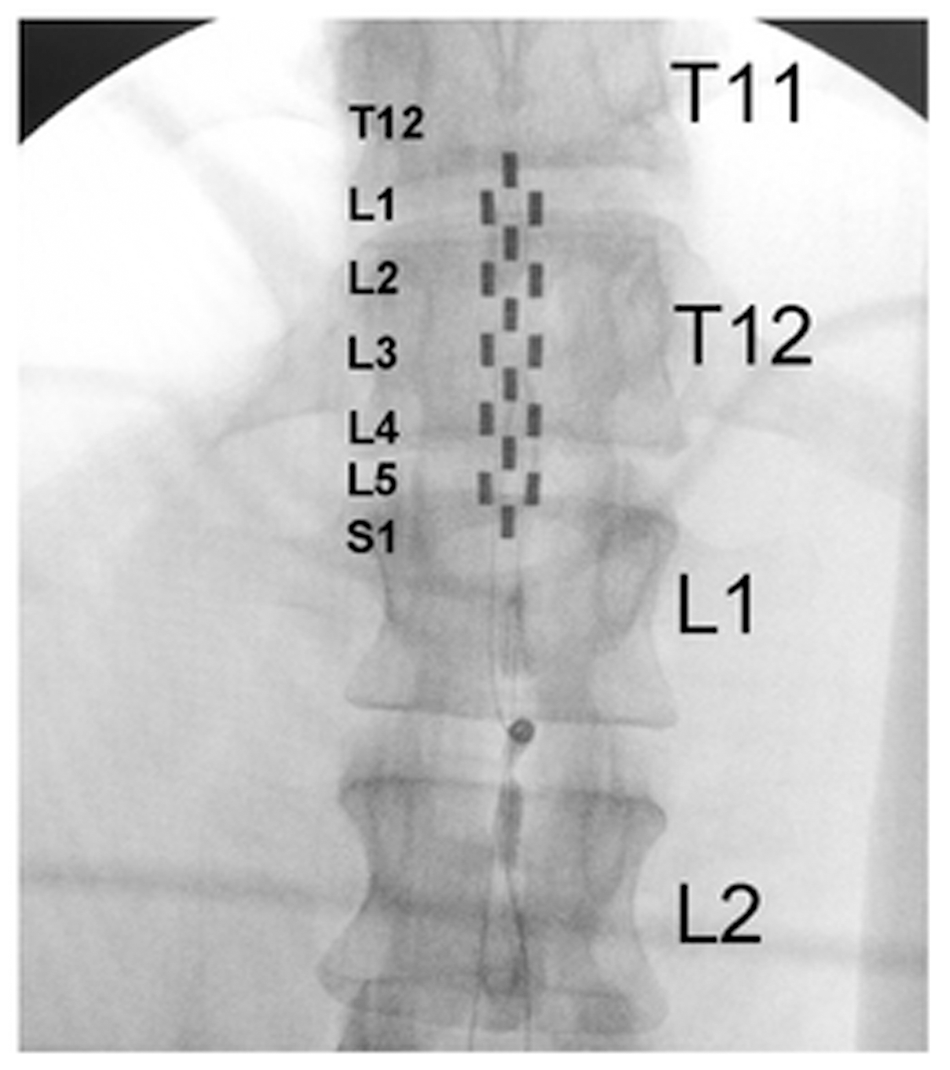

Four research participants with chronic motor complete, cervical SCI were studied (Table 1). All individuals were clinically stable, presented with orthostatic hypotension, persistent low resting blood pressure, and routine symptoms of autonomic dysreflexia with no cardiovascular disease unrelated to SCI. The research participants signed an informed consent prior to participating in the study. The study protocol and informed consent were approved by the University of Louisville Institutional Review Board in accordance with the Declaration of Helsinki. A 16-electrode array (5-6-5 Specify, Medtronic, Minneapolis, MN, United States) was implanted to span the spinal cord segments L1–S1 (vertebrae T11–L1) in all research participants (Figure 1), as previously described (Harkema et al., 2011; Angeli et al., 2014). The electrode lead was tunneled subcutaneously and connected to the pulse generator (RestoreADVANCED, Medtronic, Minneapolis, MN, United States) placed ventral in the abdomen.

FIGURE 1. Fluoroscopy showing electrode array location relative to thoracic and lumbar vertebrae. Large letters T11, T12, L1, and L2 identify thoracic and lumbar vertebrae; small letters L1–S1 identify the spinal cord levels estimated by mapping with motor-evoked potentials.